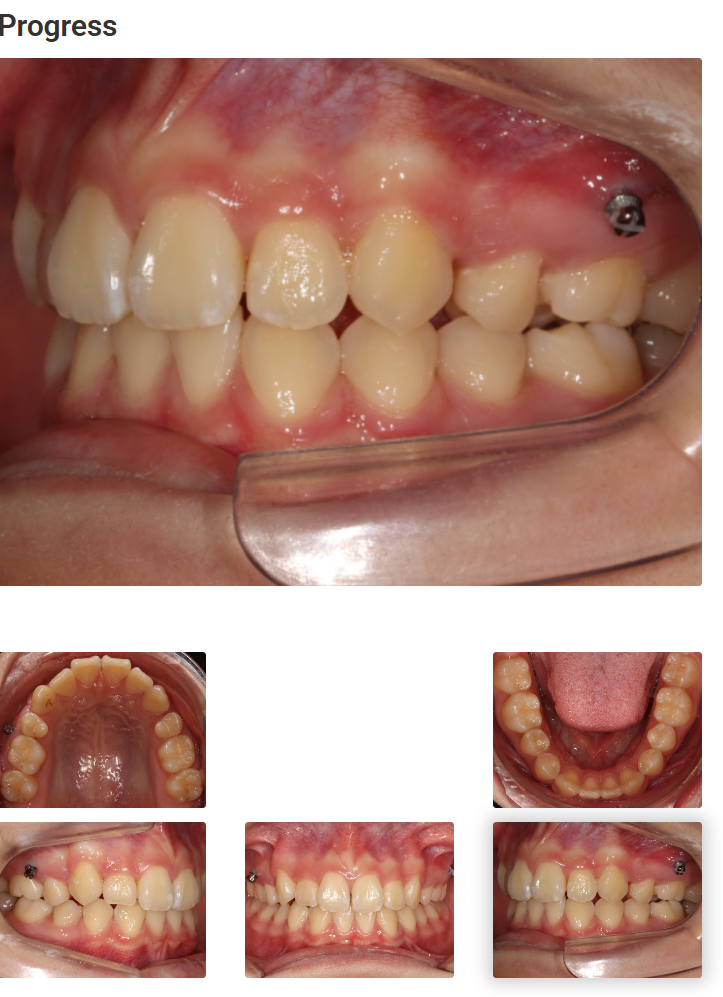

치료 중간 과정

치료 중간의 모습입니다.

양쪽에 심어져 있는 미니스크류가 보이실 겁니다.

인비절라인 치료에도 미니스크류가 필요한 경우가 많습니다.

12개월동안의 치료 모습입니다.

아래쪽은 선천적으로 앞니 두개가 없었습니다.

그래서 원래는 위아래 2개씩, 총 4개를 빼고 하는것이 일반적인 진단일 수 있지만

이 환자분은 위에만 두개를 뺐습니다.

반대쪽을 보시면 덧니가 해결된 것을 확인 할 수 있네요